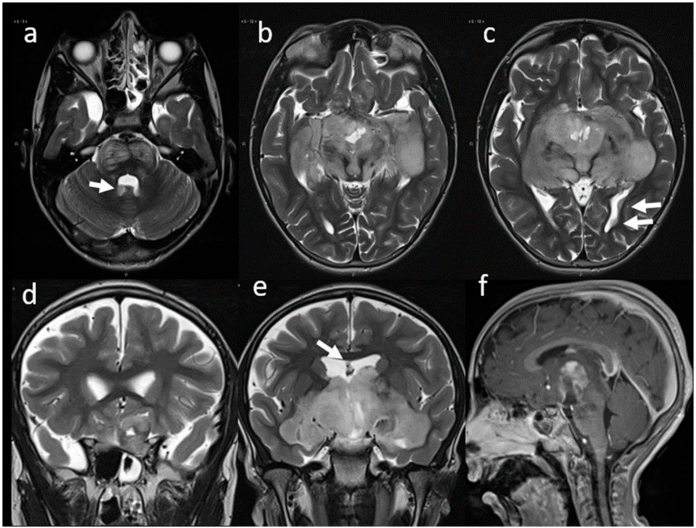

治疗近一年后,患者开始表现出恶病质的临床表现,脑部MRI显示疾病进展(图2)。重新进行眼科评估,双侧完全性视力低下导致视力进一步下降。因此,开始了二线化疗,辅助靶向治疗。五年后(8岁),患者出现嗜睡,但能被言语或触觉刺激唤醒,清醒时方向良好。进行了脑部计算机断层扫描(CT)和新的核磁共振成像,显示病情稳定。

图2. 核磁共振成像。疾病进展时的T2w轴向(a–c)和冠状(d,e)图像。信号特性基本上没有变化。矢状Gd T1w(f)图像显示鞍上肿块的不均匀对比增强部分减少。